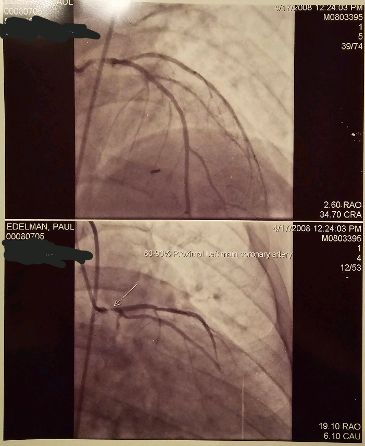

Every year, the prior week is so difficult for me emotionally. Of all the things that I have dealt with in my life, especially with my health, including my battle with cancer, Hodgkin’s Lymphoma back in 1998, it is my emergency heart bypass in 2008 that carries the most weight with my thoughts each year. Even everything that I went through with my divorce, which I consider an experience worse than all of my health issues combined, it is my bypass, every year, I am reminded, how close to dying I really was. My cardiologist even told me so, “it’s not a question if you are going to die from a fatal heart attack, but when.”

My lifestyle went from “work can’t do without me” and “my family can’t do without me,” to “they did do without me” at least for a short time. The fact that I lived my life with the “can’t do without me” mantra for so long, ignoring the chest tightness I had for four months, whether I was mowing my lawn, shoveling snow, moving equipment at work, or carrying either of my daughters, could have ended my life at any time. The other things I dealt with my health and divorce, though not pleasant, they were not likely to be as final as a fatal heart attack.